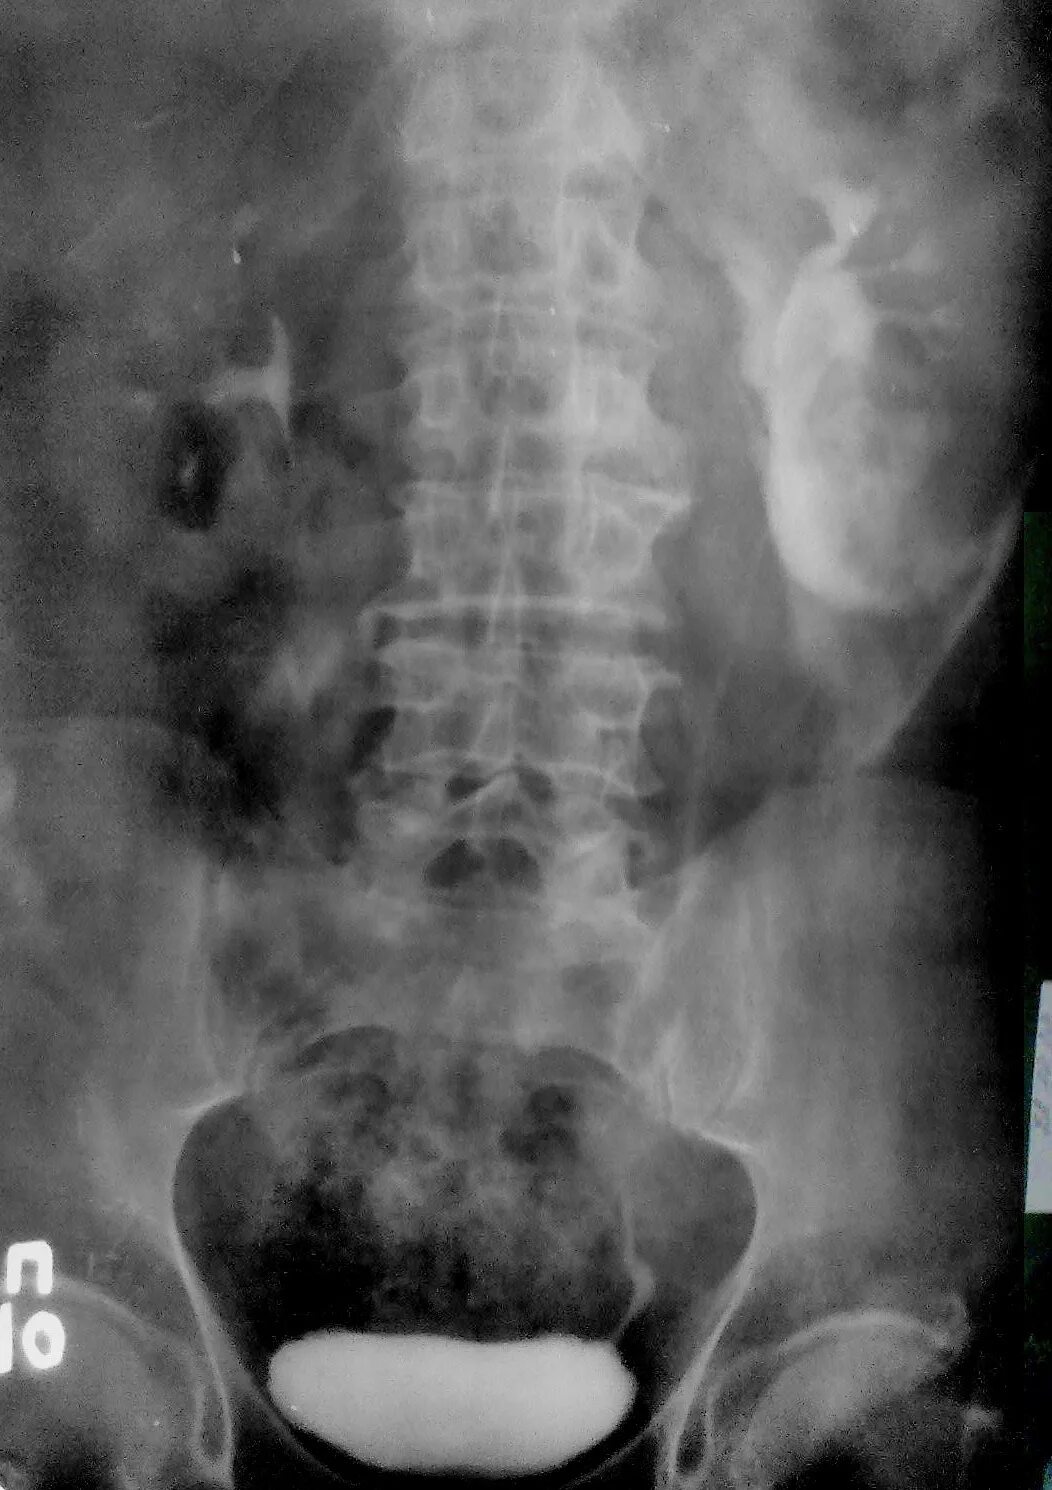

Как делается урография